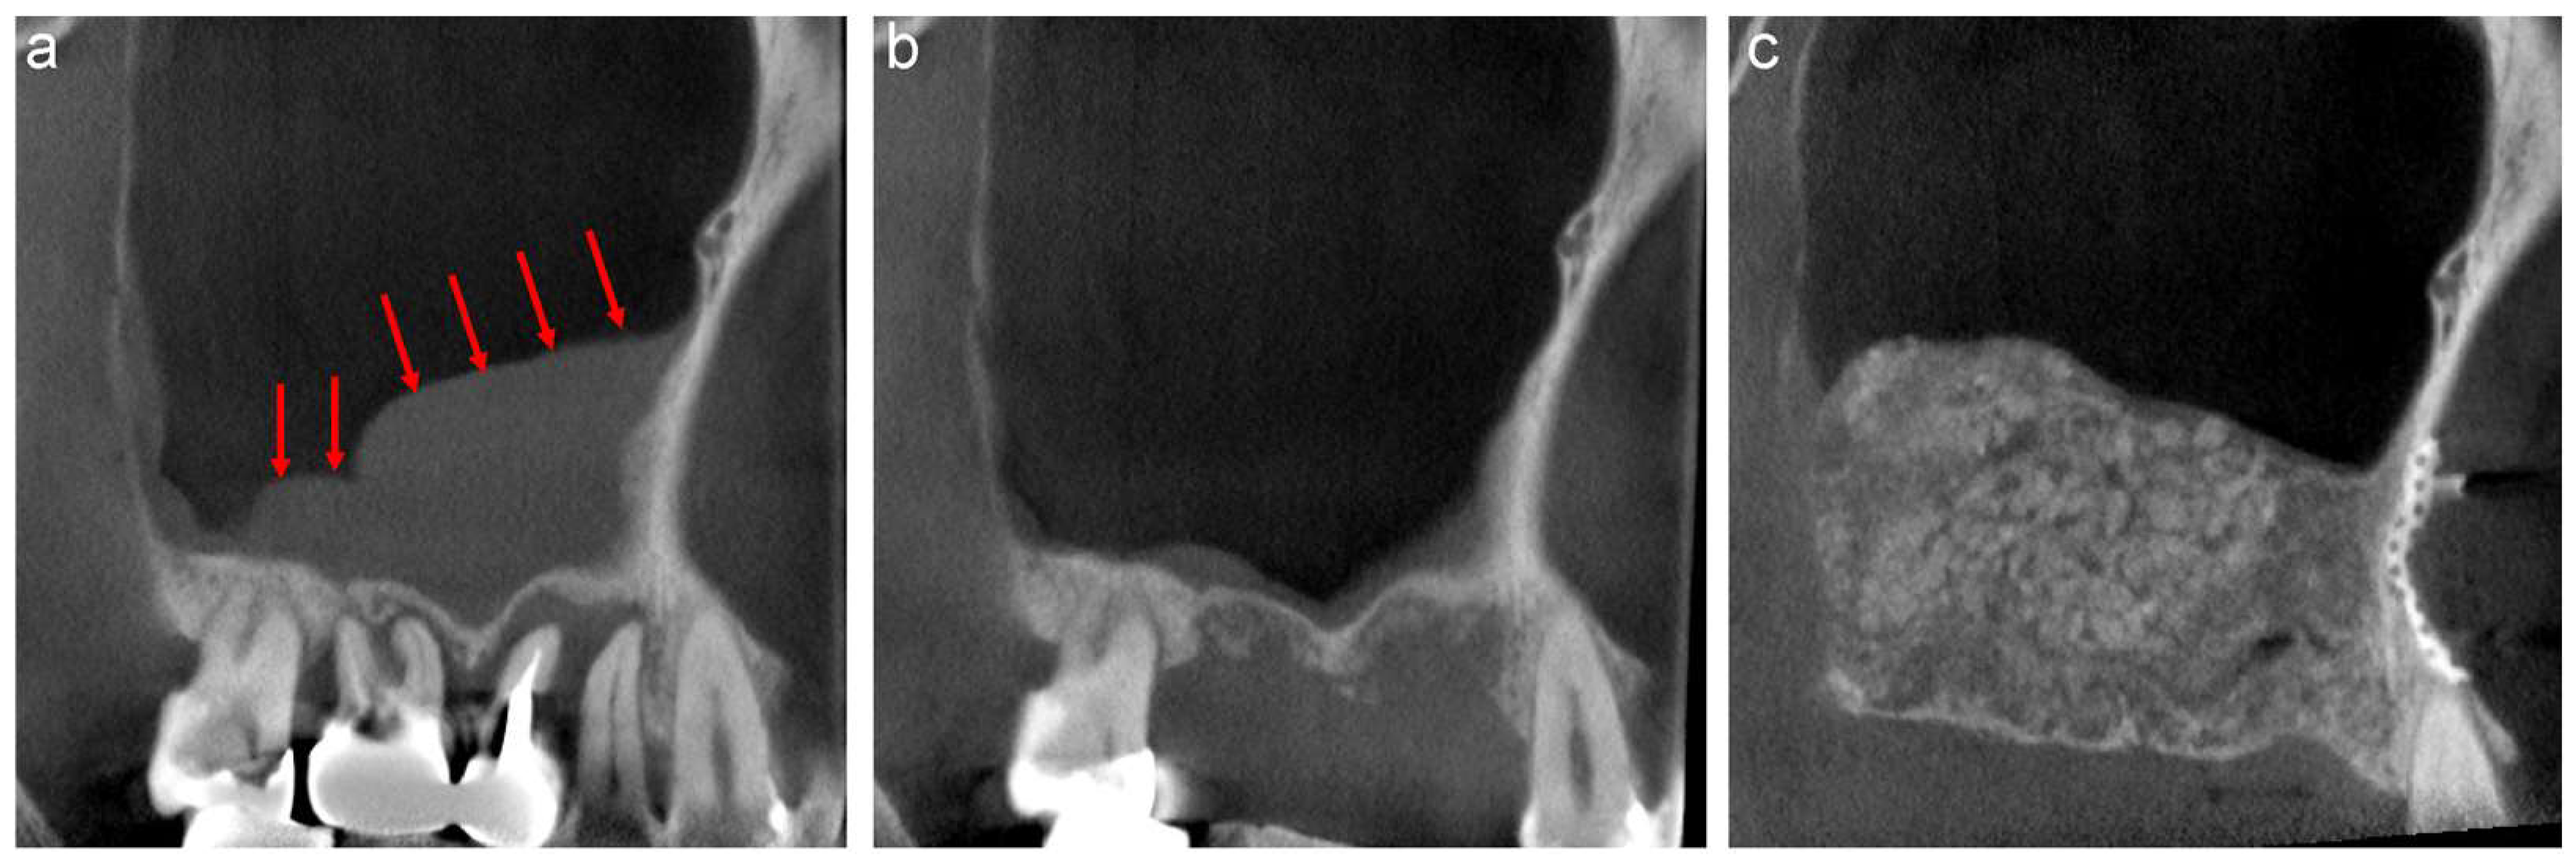

3.1.1. Case 1

A 58-year-old male was referred to our clinic by his dentist for implant treatment of the right maxilla in 2018. Well-defined, faintly radiopaque antral lesions were observed on the mesiodistal section of the CT image acquired at the first visit. Moreover, marked alveolar bone resorption was observed in the regions surrounding 16, 15, and 14 (Figure 1a, red arrows). The requirement for extraction of these teeth and sinus floor elevation for implant treatment was explained to the patient. The well-defined, faintly radiopaque antral lesions were found to have disappeared on the CT image acquired 3 months after the extractions (Figure 1b); thus, sinus floor elevation was performed using β-TCP granules (Osferion; Olympus Terumo Biomaterials, Tokyo, Japan) alone and 17 was extracted simultaneously at our clinic. CT images acquired 6 months postoperatively revealed a radiopaque area at the site that underwent sinus floor elevation. Swelling of the sinus membrane was not observed (Figure 1c).

Figure 1.

The mesiodistal section of CT images of the right maxillary sinus. (a) Antral, well-defined, faintly radiopaque lesions (red arrows) and marked alveolar bone resorption are observed near 16, 15, and 14. (b) The well-defined, faintly radiopaque antral lesions disappeared 3 months after extraction. (c) A radiopaque area is observed at the sinus floor elevation without swelling of the sinus membrane six months postoperatively.

3.1.2. Case 2

A 44-year-old female scheduled to undergo implant placement for the replacement of 27 was referred to our clinic in 2014 for sinus floor elevation owing to insufficient bone height. A well-defined, faintly radiopaque antral lesion was observed on the mesiodistal section of the CT image acquired at the first visit (Figure 2a, red arrows). A periapical lesion was observed at the palatal root apex of 26, indicating periapical disease (Figure 2a, yellow arrow); consequently, the tooth was extracted by the original dentist. The antral radiopaque lesion had disappeared almost completely four months after the extraction (Figure 2b). Thus, sinus floor elevation was performed using β-TCP granules alone at our clinic. CT image acquired nine months postoperatively revealed a radiopaque area at the site where sinus floor elevation was performed without swelling of the sinus membrane (Figure 2c).

Figure 2.

The mesiodistal section of CT images of the left maxillary sinus. (a) Well-defined, faintly radiopaque antral lesions (red arrows) and bone resorption at the palatal root apex of 26 (yellow arrow) are observed. (b) Almost all well-defined, faintly radiopaque antral lesions had disappeared four months after the extraction. (c) A radiopaque area is observed at the sinus floor elevation without swelling of the sinus membrane nine months postoperatively.